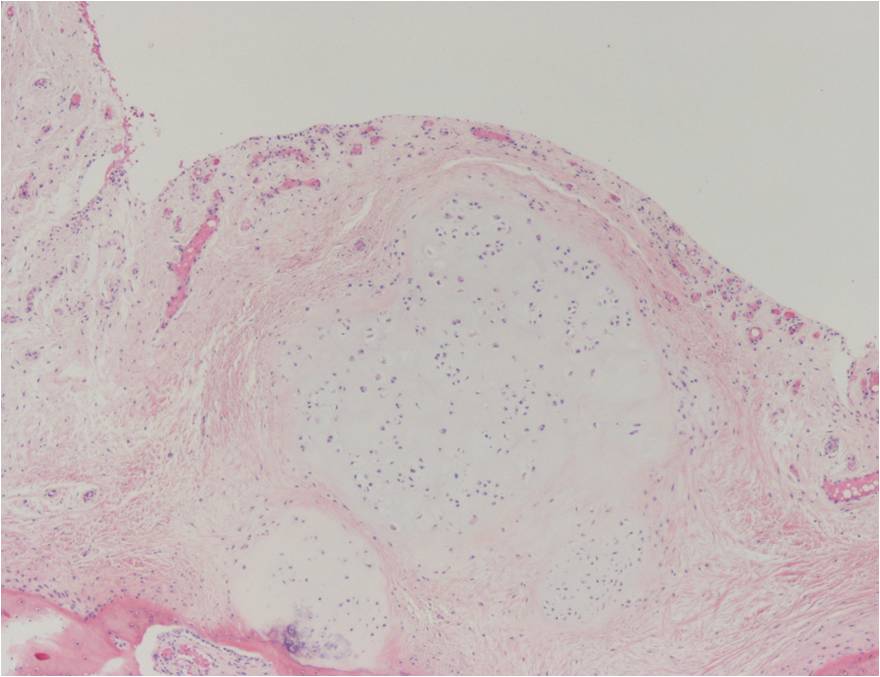

Synovial chondromatosis is an uncommon, benign, process that occurs in large joints, such as the knee (50%), hip, elbow, or shoulder. This process mainly affects synovium and hence most commonly arises from joints and tendons which are lined by synovium. Synovial Chondromatosis may also affect bursae and extend into surrounding soft tissues. This condition is seen in patients between 20 and 50 years of age and most commonly in men (male-female ratio of 2-4/1). The patient usually complains of pain, stiffness, crepitance, swelling, and joint locking. The knee is the most common site to be affected. Symptoms are long-standing and progressive. The plain x-ray may be normal (5 to 33%) or there may be small flecks of calcification (Fig. 1 & 2). On MRI the nodules of cartilage are easily seen. MR imaging may also show synovial thickening, joint erosions and intraarticular calcifications. The signal characteristics of these intraarticular bodies depend of their composition. If mineralization is not present the signal intensity follows the cartilage signal with intermediate signal on T1 images and high signal on T2 weighted MR images. Uniformly calcified bodies follows bone density on all sequences with bone marrow signal centrally and low signal peripherally (Fig. 3-5). Histologically the cartilage is arranged in nodules, which are quite cellular (Fig. 7-9). Synovial lining is present surrounding the cartilage nodules (Fig. 8). The cartilage nodules are often referred to as loose bodies however they are not really loose and embedded in the synovium lining. This is considered a metaplastic condition as opposed to a true neoplastic condition. Rarely it may turn into a malignancy usually a low grade chondrosarcoma. Malignant change is suggested by deep erosions into adjacent bone.

Fig. 7 – 9. Microscopic Pathology. Low (Fig. 7) and intermediate (Fig. 8 & 9) magnification demonstrates nodules of cartilage with high cellularity. Synovial lining is present surrounding the cartilage nodules.